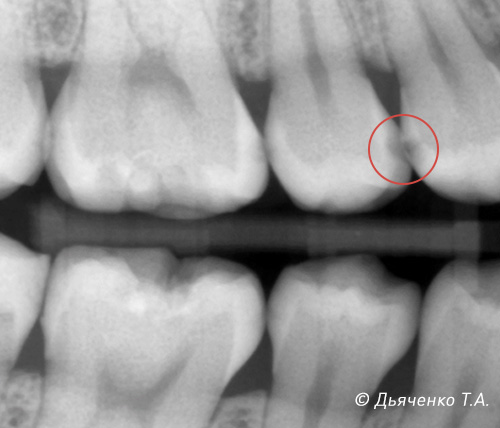

Также важна рентген-диагностика контактных пунктов Bite Wing (рис. 6 и 7). Это методика, когда, используя всего 2 рентгеновских (визиограф) снимка, мы можем просмотреть межзубные промежутки верхней и нижней челюсти с 2-х сторон.

Бывают ситуации, когда рентгенологически я вижу кариес в стадии пятна между зубами, а после 7-дневной сепарации обнаруживается глубокий кариозный процесс — кариес дентина. (Рис. 13, 14).

В таком клиническом случае (рис. 14) лечение будет классическое, препарирование, очистка с последующим восстановлением фотокомпозитным материалом.